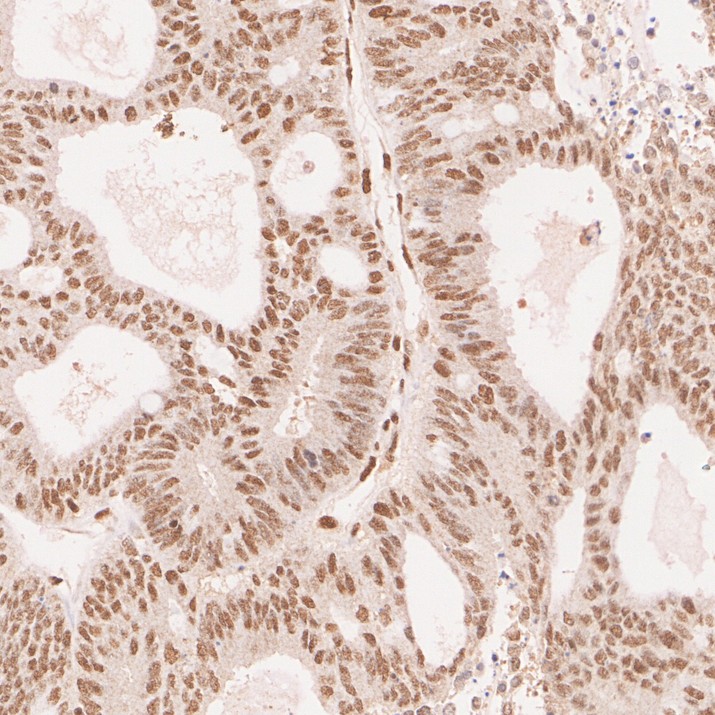

Immunohistochemical analysis of paraffin-embedded human colon carcinoma tissue with Rabbit anti-MLH1 antibody (HA721325) at 1/1,000 dilution.

The section was pre-treated using heat mediated antigen retrieval with sodium citrate buffer (pH 6.0) (high pressure) for 2 minutes. The tissues were blocked in 1% BSA for 20 minutes at room temperature, washed with ddH2O and PBS, and then probed with the primary antibody (HA721325) at 1/1,000 dilution for 1 hour at room temperature. The detection was performed using an HRP conjugated compact polymer system. DAB was used as the chromogen. Tissues were counterstained with hematoxylin and mounted with DPX.